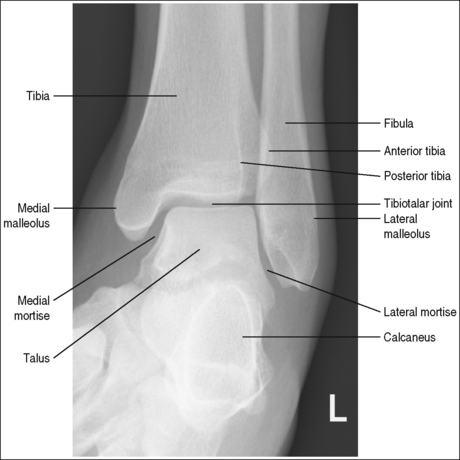

See Figure 6-46 and Box 6-10.

The ankle is demonstrated in an AP projection. The medial mortise (tibiotalar articulation) is open, and the distal tibia and talus are superimposed over the distal fibula by a small amount (0.125 inch [3 mm]), closing the lateral mortise (fibulotalar articulation).

• An AP projection of the ankle is obtained by positioning the patient supine on the image table, with the leg fully extended and the foot dorsiflexed until its long axis is placed in a vertical position (Figure 6-47). In this position, the intermalleolar line (imaginary line drawn between the medial and lateral malleoli) is at a 15- to 20-degree angle with the IR. The medial malleolus is positioned farther from the IR than the lateral malleolus.

• Evaluating the openness of the tibiotalar joint. On an AP ankle projection, determine whether an open joint was obtained and whether the tibia is demonstrated without foreshortening by evaluating the anterior and posterior margins of the distal tibia. On an AP ankle projection with accurate positioning, the anterior margin is demonstrated approximately 0.125 inch (3 mm) proximally to the posterior margin (see Figure 6-48). If the proximal lower leg was elevated or the central ray was centered proximal to the tibiotalar joint, the anterior tibial margin is projected distally, resulting in a narrowed or obscured tibiotalar joint space (see Image 34). If the distal lower leg was elevated or the central ray was centered distal to the tibiotalar joint, the anterior tibial margin is projected more proximally to the posterior margin than on an AP ankle projection, expanding the tibiotalar joint space and demonstrating the tibial articulating surface (see Image 35).

The tibiotalar joint space is at the center of the exposure field. The distal fourth of the tibia and fibula, the talus, and the surrounding ankle soft tissue are included within the collimated field.

• To place the tibiotalar joint in the center of the image, center a perpendicular central ray to the ankle midway between the malleoli. The medial malleolus is located at the same level as the tibiotalar joint space. Open the longitudinal collimation to include the calcaneus and one fourth of the distal lower leg. Transverse collimation should be to within 0.5 inch (1.25 cm) of the ankle skin line.